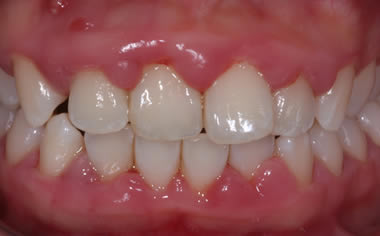

Gum disease

Case One (2 images)

Treatment of severe gum disease.